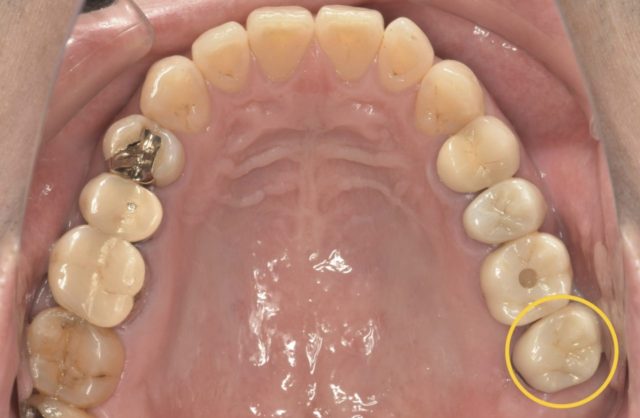

こちらが治療後のレントゲンです。

現在は、仮歯で経過観察を行なっていますが、もともとあった違和感も治療後すぐに無くなり、経過良好です!

経過観察が終われば、セラミックスの被せ物を入れる予定です。